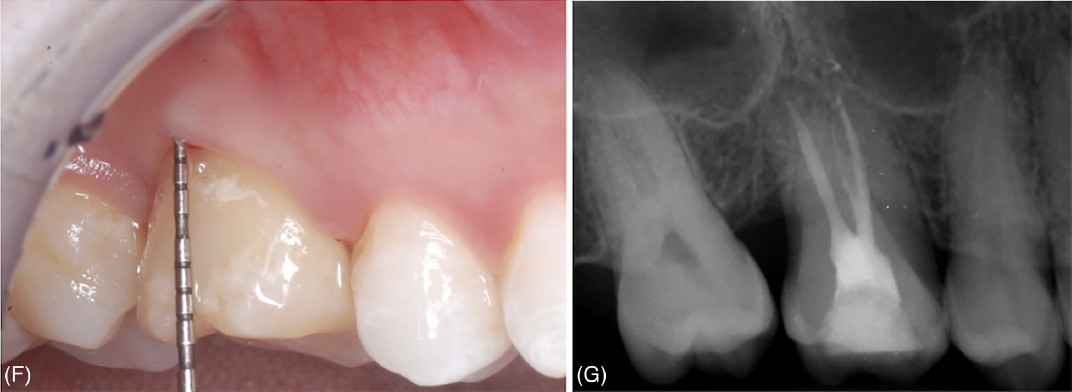

Фото 2. Удаление зуба 46 и его замещение с использованием зуба 48. (F) Клиническое обследование через 24 месяца наблюдения. (G) Прицельная рентгенограмма через 24 месяца наблюдения

Фото 3. Удаление зуба 16 и его замещение с использованием зуба 18. (F) Клиническая картина через 24 месяца; зондирование показывает, что значительная часть щечного прикрепления, отсутствовавшая при первом визите, восстановилась. (G) Рентгенологическая картина через 24 месяца

При контрольном визите через 24 месяца подвижность и фуркационные поражения выявлены не были; значения глубины зондирования ≤ 4 мм были зафиксированы во всех точках обоих донорских зубов. Рентгенологических признаков резорбции корня, анкилоза или периапикальных/ периодонтальных очагов поражения обнаружено не было; уровень костной ткани у обоих донорских зубов составил более 50% длины корня.